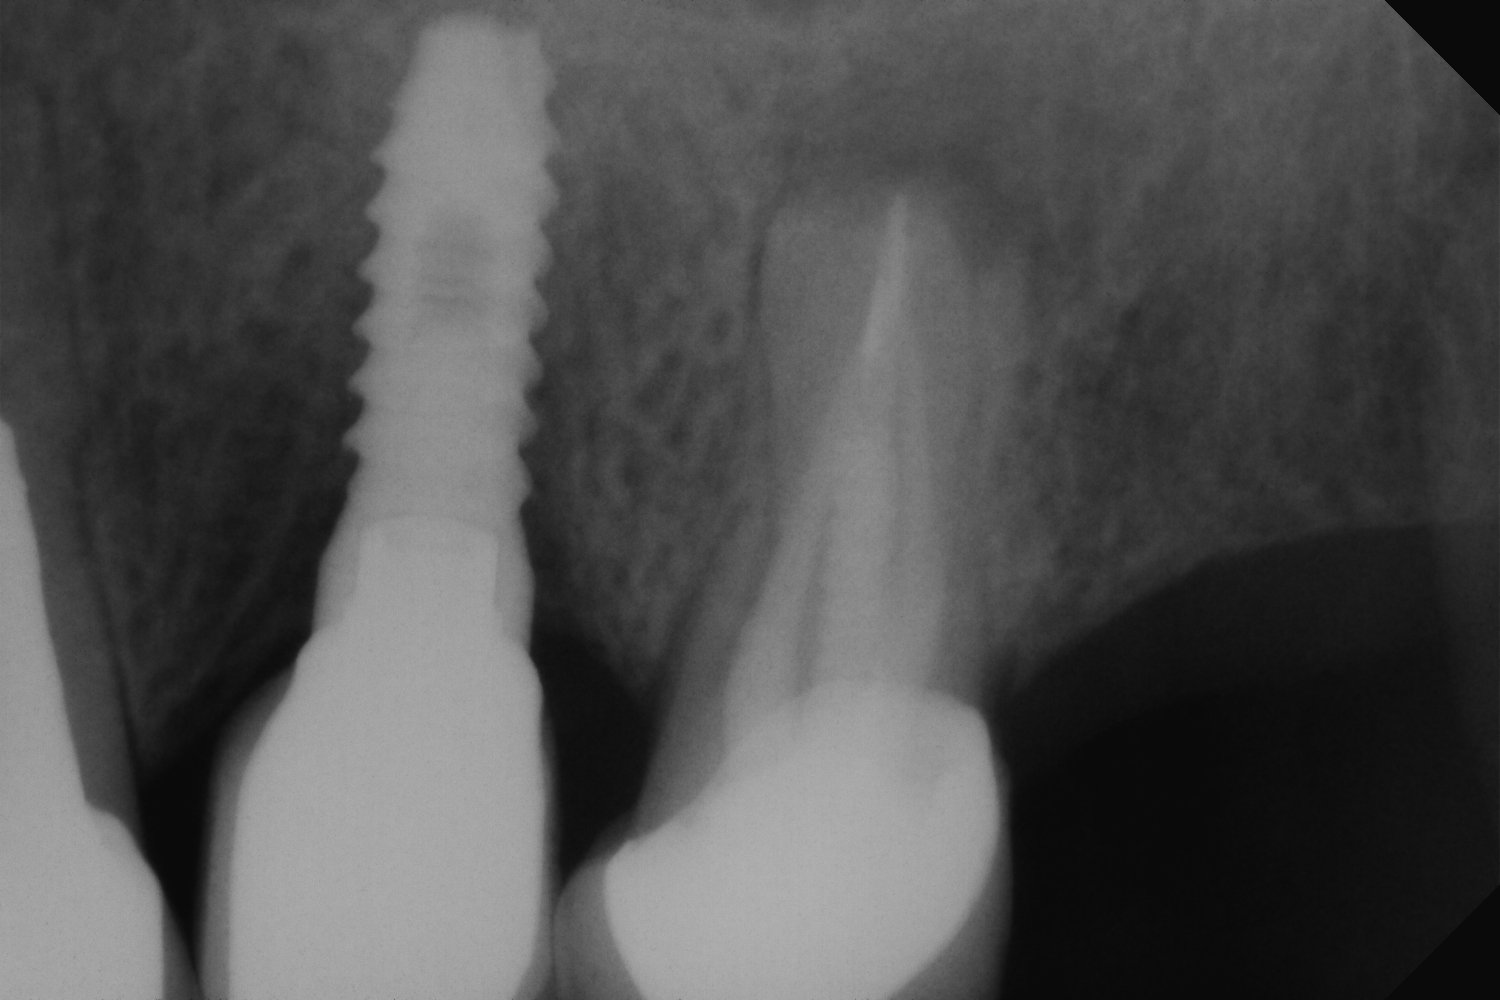

Buenas tardes, muchas gracias por vuestra labor, creo que estos dos implantes son eckerman all spiral, me podríais ayudar respecto a la plataforma y compatibilidades?? saludos